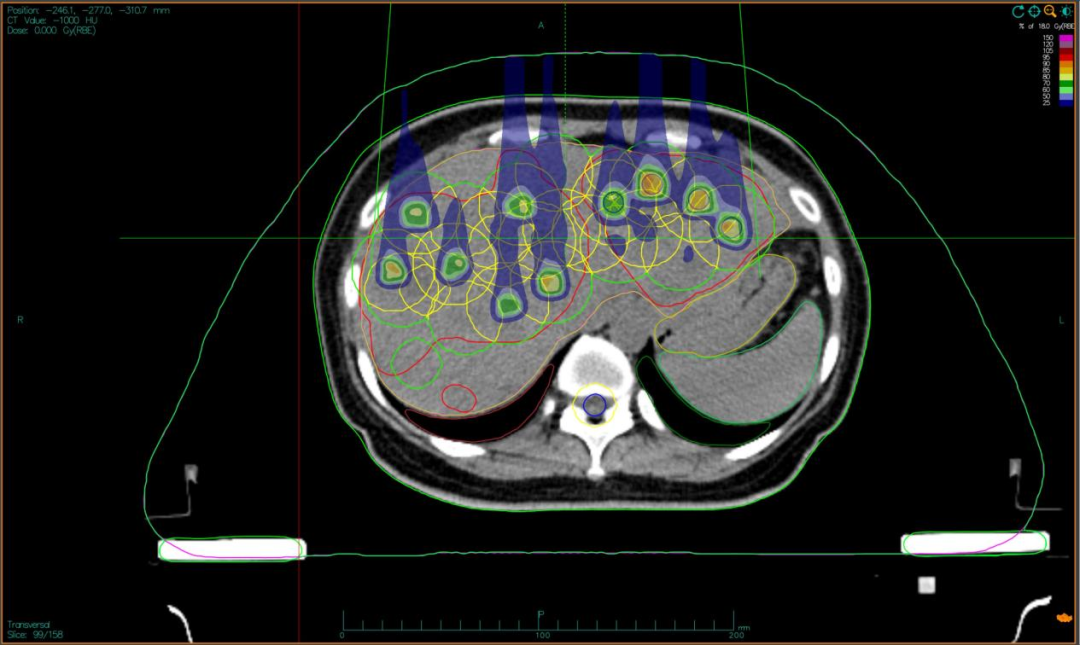

“双布拉格”,并非指代两个物理峰值,而是两大核心治疗理念的深度碰撞与融合。第一个“布拉格”,是物理学范畴的布拉格峰——重离子束流可在体内特定深度释放绝大部分能量,这一特性构筑起“指哪打哪”、极致保护正常组织的物理基石。第二个“布拉格”,是免疫学范畴的布拉格治疗,即国际前沿的PRaG协同治疗方案。它通过精准放疗在局部“点火”,释放肿瘤抗原;以GM-CSF为“导航”,引导免疫系统识别肿瘤细胞;再借助PD-1抑制剂“解除免疫刹车”,让免疫细胞能够持久、全身性地攻击肿瘤,最终追求珍贵的“远隔效应”。而晶格放疗,正是连接两大“布拉格”理念的关键桥梁。针对常规手段无法照射的巨大肿瘤,它将均匀剂量场转化为无数离散的高剂量“能量岛屿”。这种模式不仅能奇迹般保护穿插其中的正常组织与脉管结构,其独特的剂量分布,更被证实可高效诱发免疫原性细胞死亡,将物理打击的能量,转化为激活全身免疫反应的“信号”,让肿瘤的局部治疗与全身控制成为现实。

四大优势协同发力:一,依托重离子射线特有的“布拉格峰”物理特性,实现对深部肿瘤的“定点爆破”;二,采用“晶格放疗”先进布野技术,在巨大肝肿瘤内部精准布设能量“棋盘格”,在高效杀伤肿瘤细胞的同时,为残存正常肝组织与关键脉管留存生存空间;三,将此次精准物理打击,完美嵌入“布拉格治疗”免疫协同策略,以此作为激活全身免疫反应的“点火器”,联合PD-1抑制剂与GM-CSF,力求激发远隔效应,对未被照射的病灶形成攻击;四,引入干细胞支持下的新一代免疫细胞疗法,整合诱导多能干细胞(iPSCs)或间充质干细胞(MSCs)来源的免疫效应细胞(如CAR-T、CAR-NK和TCR-T细胞)与工程化技术,显著提升癌症免疫治疗的可及性与疗效。